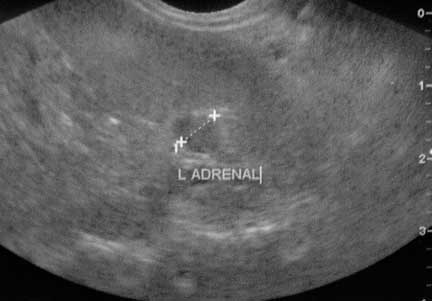

Ultrasound

Ultrasound is very important to us. This is an enlarged adrenal gland in a ferret with Adrenal Gland disease.

We have more information on ultrasound in animals at this link.